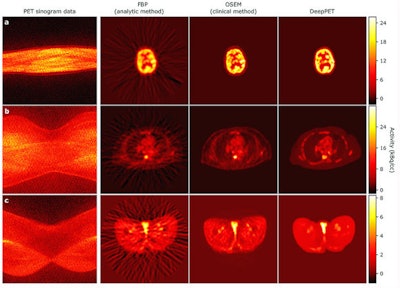

Most importantly, the final qualitative test involved real clinical data from two separate PET/CT scanners (Discovery 710 and Discover 690, GE Healthcare). The clinical 3D PET images were converted into 2D slice sinograms, which were reconstructed through filtered back projection (FBP) and OSEM. The results were then inputted into DeepPET. Among the criteria used to evaluate image quality was the structural similarity index (SSIM) for visual assessment.

The series of PET images includes the cross sections of a brain (top), abdomen (middle), and hip (bottom). Each row depicts network input prior to reconstruction (sinogram), an older interpretation of data (FBP), the current method of interpretation (OSEM), and DeepPET, which produces smoother images and sharper detail compared with the other methods. Images courtesy of Häggström et al.

The series of PET images includes the cross sections of a brain (top), abdomen (middle), and hip (bottom). Each row depicts network input prior to reconstruction (sinogram), an older interpretation of data (FBP), the current method of interpretation (OSEM), and DeepPET, which produces smoother images and sharper detail compared with the other methods. Images courtesy of Häggström et al."By combining [radiologist] expertise with the state-of-the-art computational resources that are available here, we have a great opportunity to have a direct clinical impact," Häggström added in a statement. "The gain we've seen in reconstruction speed and image quality should lead to more efficient image evaluation, and more reliable diagnoses and treatment decisions, ultimately leading to improved care for our patients."